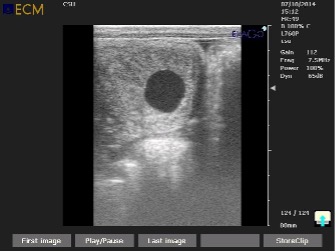

Pre-breeding checks are routine ultrasound scans of the uterus, ovaries, and other examinations to determine the optimal time to breed. This evaluation normally includes ultrasound scans, vaginal evaluation, and all the follow-ups in order to ensure the most accuracy of breeding. Each mare is treated to suit her needs and/or difficulties according to each animal's individuality.

• Ultrasound examination